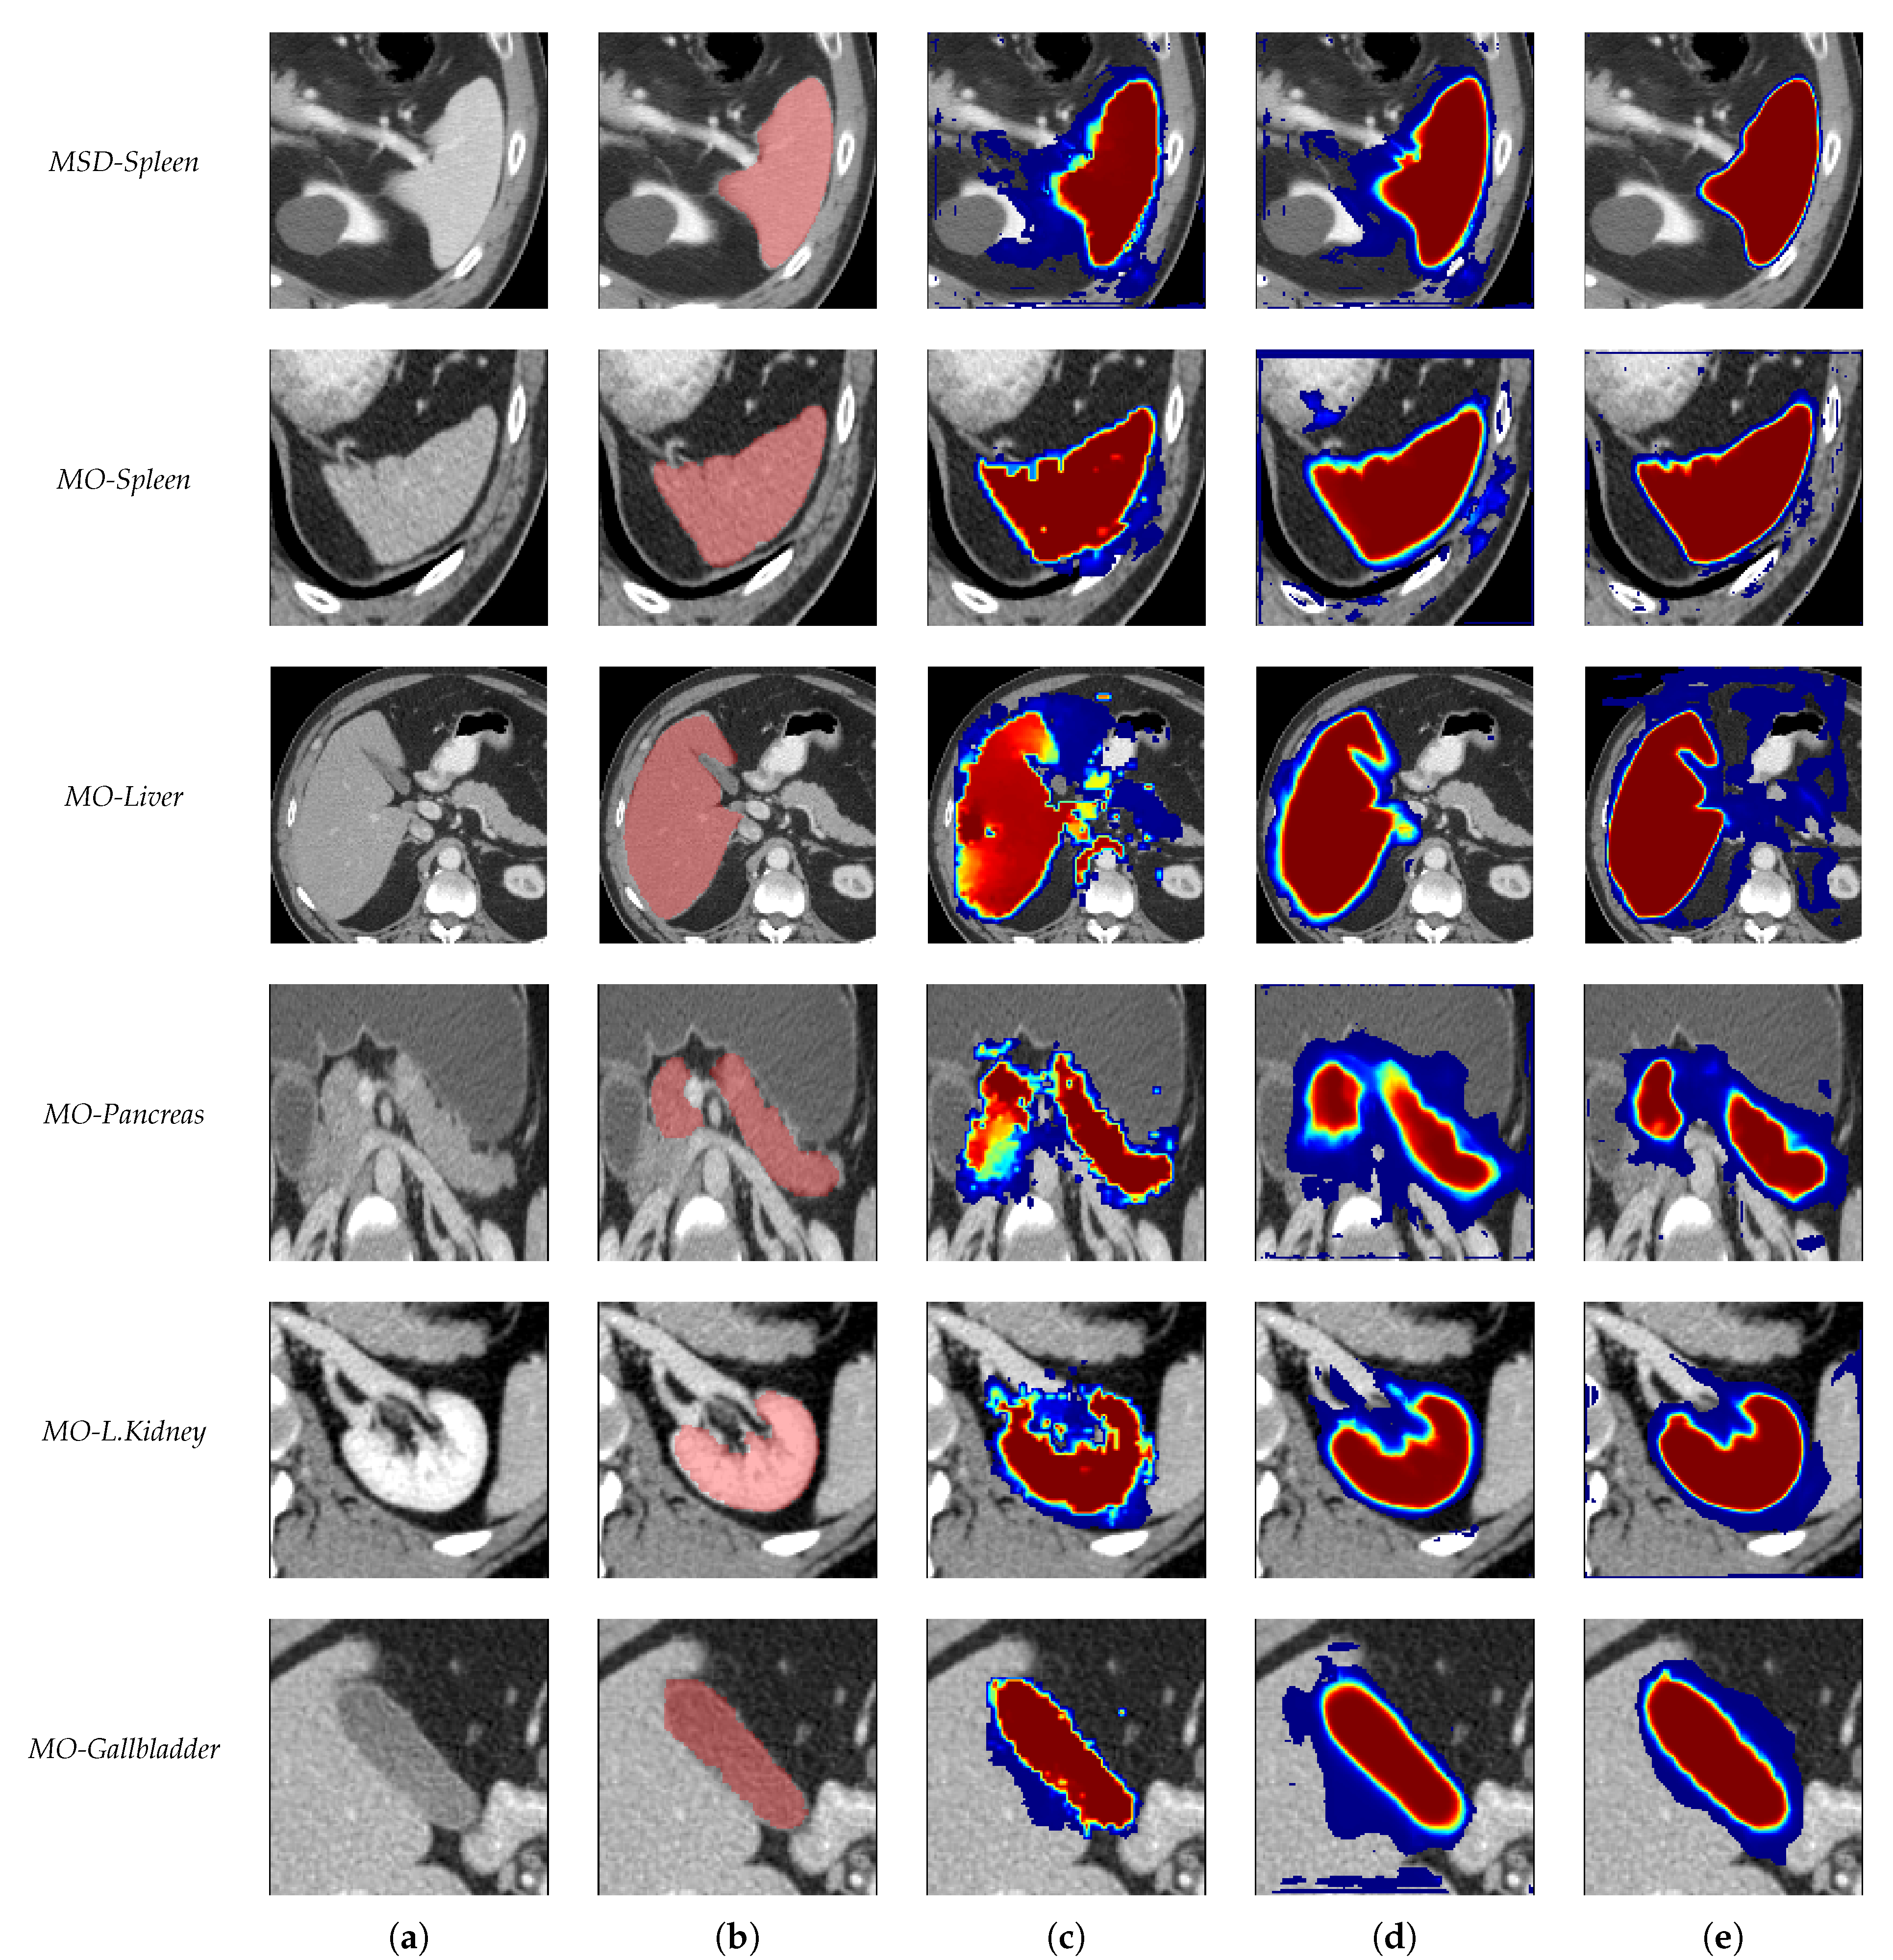

- (a)

- Without RW and Dice loss

- (b)

- With RW but without the extra point channel and Dice loss

- (c)

- With RW and Dice loss

- (d)

- With RW and Dice loss and point loss

- (e)

- With RW and Dice loss and point loss and attention